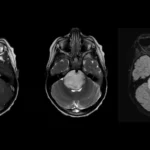

МРТ-зображення гліобластоми. Автор: Домінік Хіггінс, доктор медицини, доктор філософії